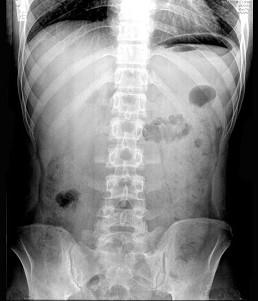

急腹症时用X线腹部透视和摄片可辅助诊断 ( )A、肠梗阻B、胃肠穿孔C、腹腔出血D、不透光胆结石或尿结石E、胰腺炎

问题 急腹症时用X线腹部透视和摄片可辅助诊断 ( )

选项 A、肠梗阻 B、胃肠穿孔 C、腹腔出血 D、不透光胆结石或尿结石 E、胰腺炎

答案 ABD